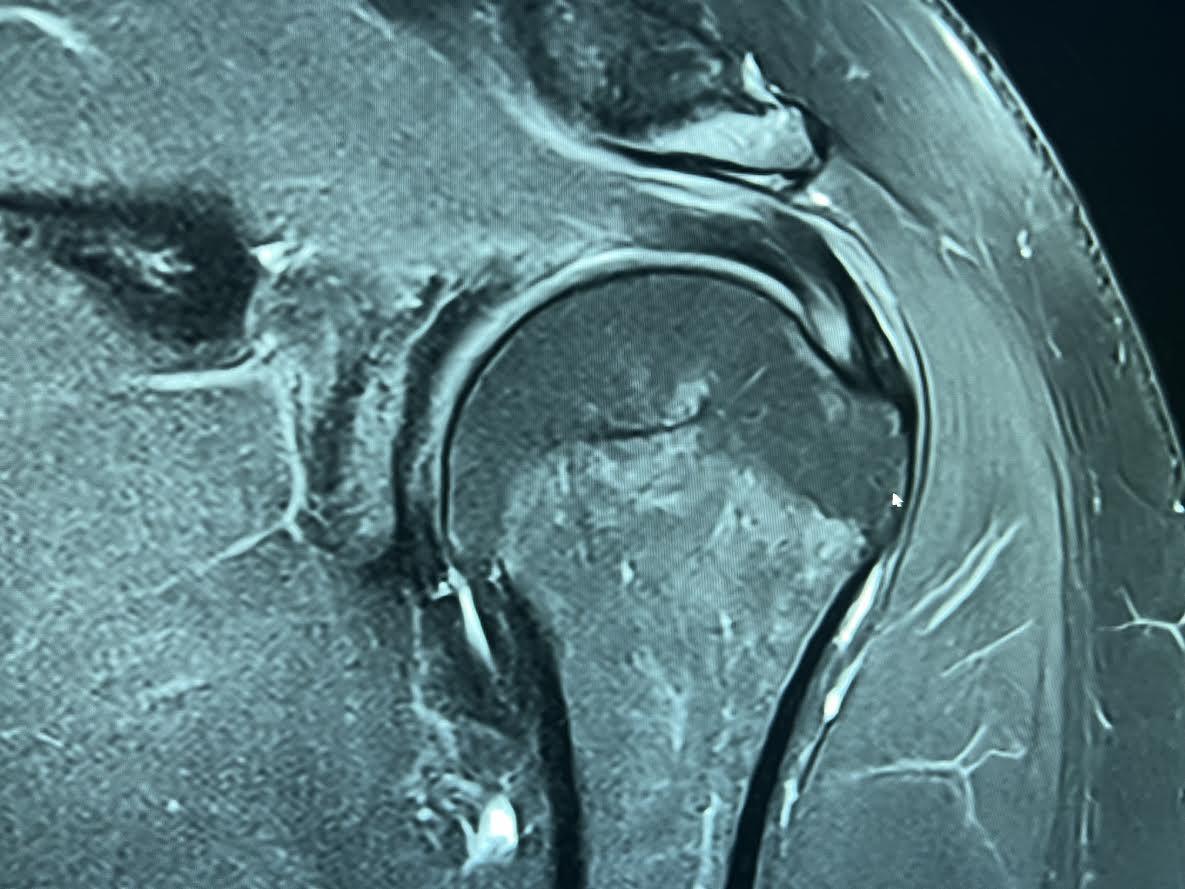

A rotator cuff tear is where the tendons that cross the humerus develop either a partial or full tear.7 A partial tear is when the tendon is thinned out but still connects the bone and muscle [Figure 4]. A full-thickness tear occurs when the tendon no longer connects the bone and muscles [Figure 5]. These two types of tears, most commonly partial articular-sided tears, are very common in tennis players’ shoulders and mainly occur from overheads and serves.8 These two shots induce substantial, degenerative damage to the rotator cuff tendon, and therefore make tennis players very prone to injury. In most cases, non-operative treatment will resolve the injury, but in severe cases, operative treatment is the only option. Non-operative treatment involves rehabilitation therapy and rest; in older patients, corticosteroid injections can help, but research has shown that in elite and youth athletes these injections are ineffective.8 Operative treatment includes debridement and partial or full rotator cuff repair. These treatment options are very rare and are only necessary in the most severe cases.